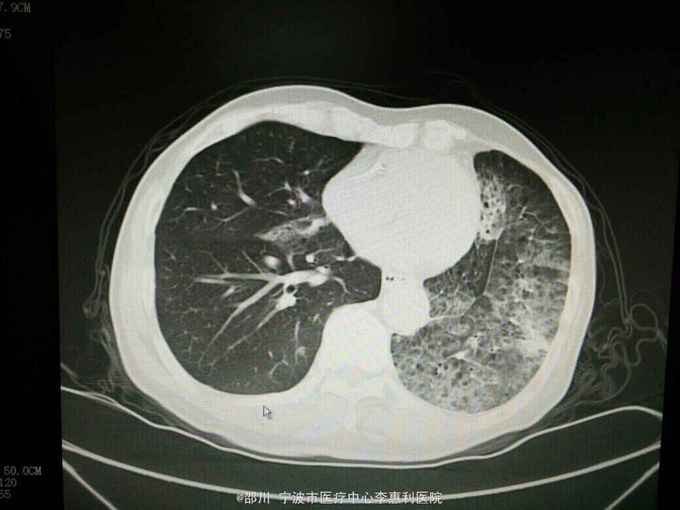

查体:神志清,精神好,生命体征平稳。两肺呼吸音清,未闻及干湿啰音。 辅查:血常规:WBC 9.0×10^9/L,NE 65.1%, Hb 152g/L, plt 246×10^9/L。血CEA 41.6ug/L。小便常规,大便常规,凝血功能,D-二聚体,肝肾功能,电解质均无明显异常。心电图,腹部B超无异常。 2015-10-30我院胸部CT见下图。